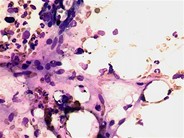

The first (and most common) clinical manifestation of acute GVHD begins with erythematous, blanching macules on the ears, palms, or soles, usually occurring at or near the time of engraftment. It is described as like a sunburn and may be pruritic or painful